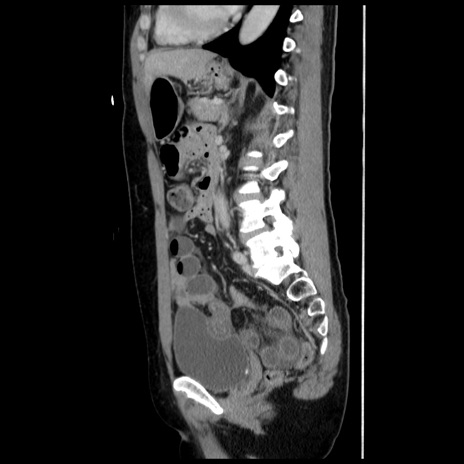

症例10(矢状断像)

【症例】 50歳代女性

【主訴】 腹痛

【現病歴】前日生レバーを食べた。今朝に排便あり。 昼前に突然発症の腹痛を生じ、当院救急外来を受診した。

【既往歴】 子宮筋腫にてで子宮全摘後

【身体所見】 意識清明、腹部:平坦、軟、下腹部やや左を中心に圧痛・反跳痛あり、筋性防御あり

【データ】WBC 7800、CRP 0.07